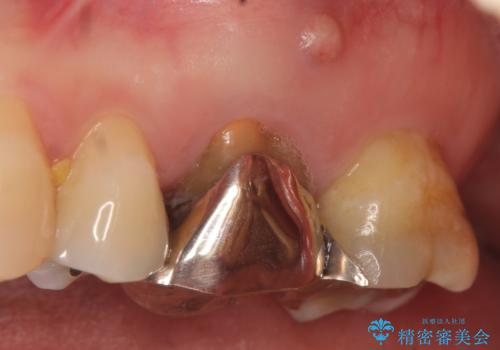

- お口の中にある銀歯を無くしたいとご相談にいらした方です。

適合の良いセラミックにてやり替えを行いました。

元々噛む力が強く、日常的に歯ぎしりもされるとの事でしたので、歯が割れてしまうリスクを軽減させるため、歯全体を覆うクラウンをメインに補綴治療を行いました。

適合不良の補綴物は二次的な虫歯発生のリスクが高まります。

自費診療で用いられる材料は保険適応の材料に比べて、より精密で適合の良い被せ物作ることができるため、長期的な虫歯のリスクを大幅に減らすことが可能です。